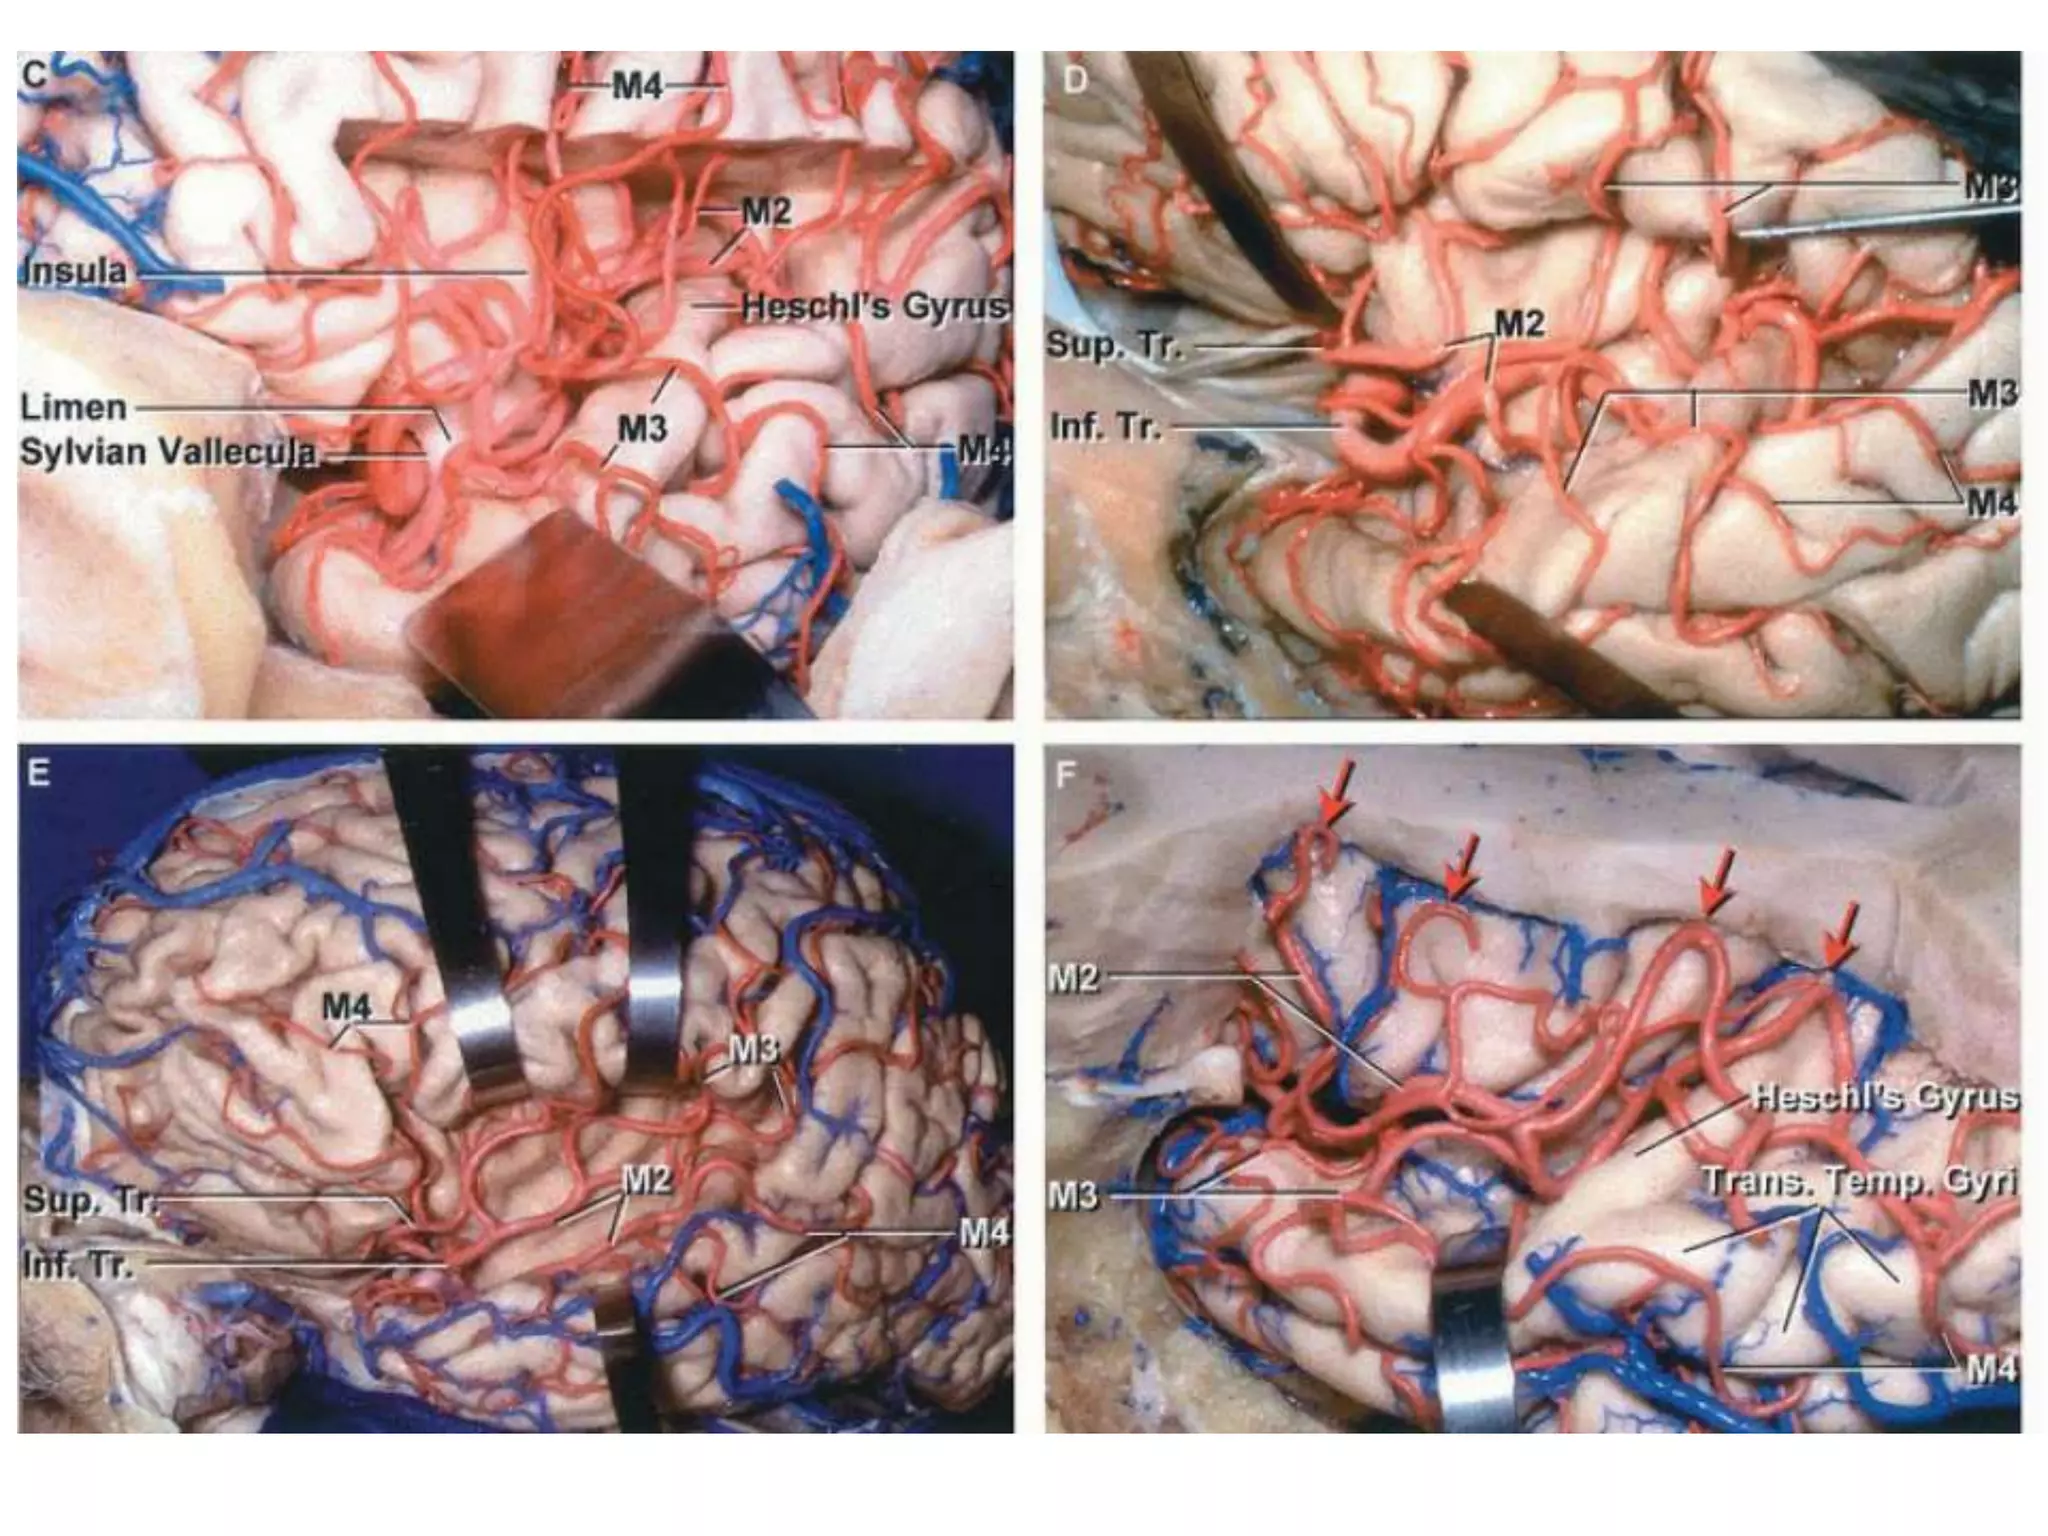

Segments

•M1 (sphenoidal),

•M2 (insular),

•M3 (opercular),

•M4 (cortical)

Exposing MCA

Sylvian fissure

Mca anatomy